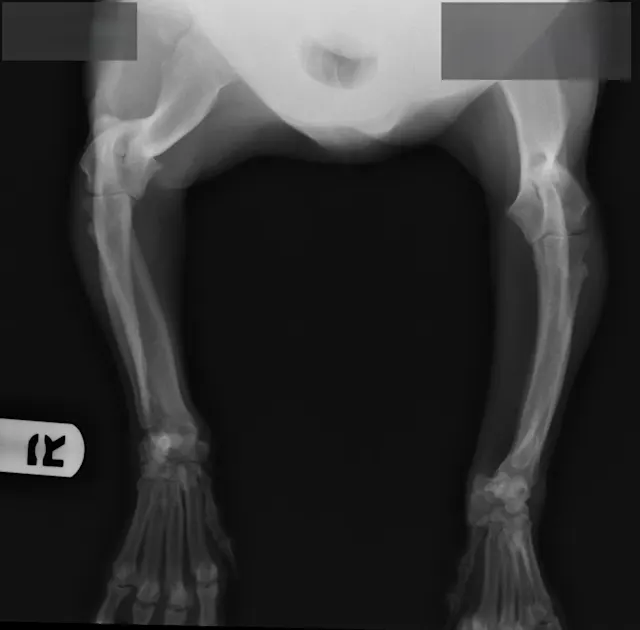

FIGURE 1

Radiographs of Ernest at 8 years of age at a recheck examination

On physical examination, Ernest had bilateral carpal valgus, with pain on manipulation of the carpus and mild hypertrophy of the shoulder musculature. On gait evaluation, slight scuffing of the left front paw was noted. Ernest also had bilateral pain/resistance on extension of the coxofemoral joints and mild atrophy of the quadriceps/hamstrings bilaterally; he also appeared to be “bunny hopping” in the hindlimbs when jogging or climbing stairs. Ernest’s BCS was 4/9, and the remainder of the examination, including a neurologic examination, was within normal limits. Ernest was diagnosed with OA and pain secondary to hip dysplasia and angular limb deformity.